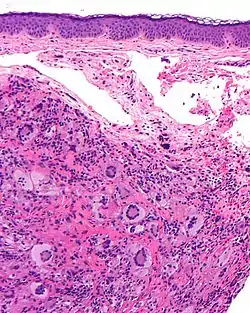

![]() صورة مجهرية للورم الحبيبي الأصفر اليافع مع خلايا توتون العملاقة .صبغة الهيماتوكسيلين والإيوسين. صورة مجهرية للورم الحبيبي الأصفر اليافع مع خلايا توتون العملاقة .صبغة الهيماتوكسيلين والإيوسين. | |